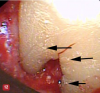

Fig 2. This image of excess cement on an implant (arrow) was taken using a glass fiber endoscope. It demonstrates the distorted and poor-quality image obtained with this instrument. A steep learning curve is associated with its clinical use because of the experience level needed to accurately interpret the images visible on the monitor.

Figure 2